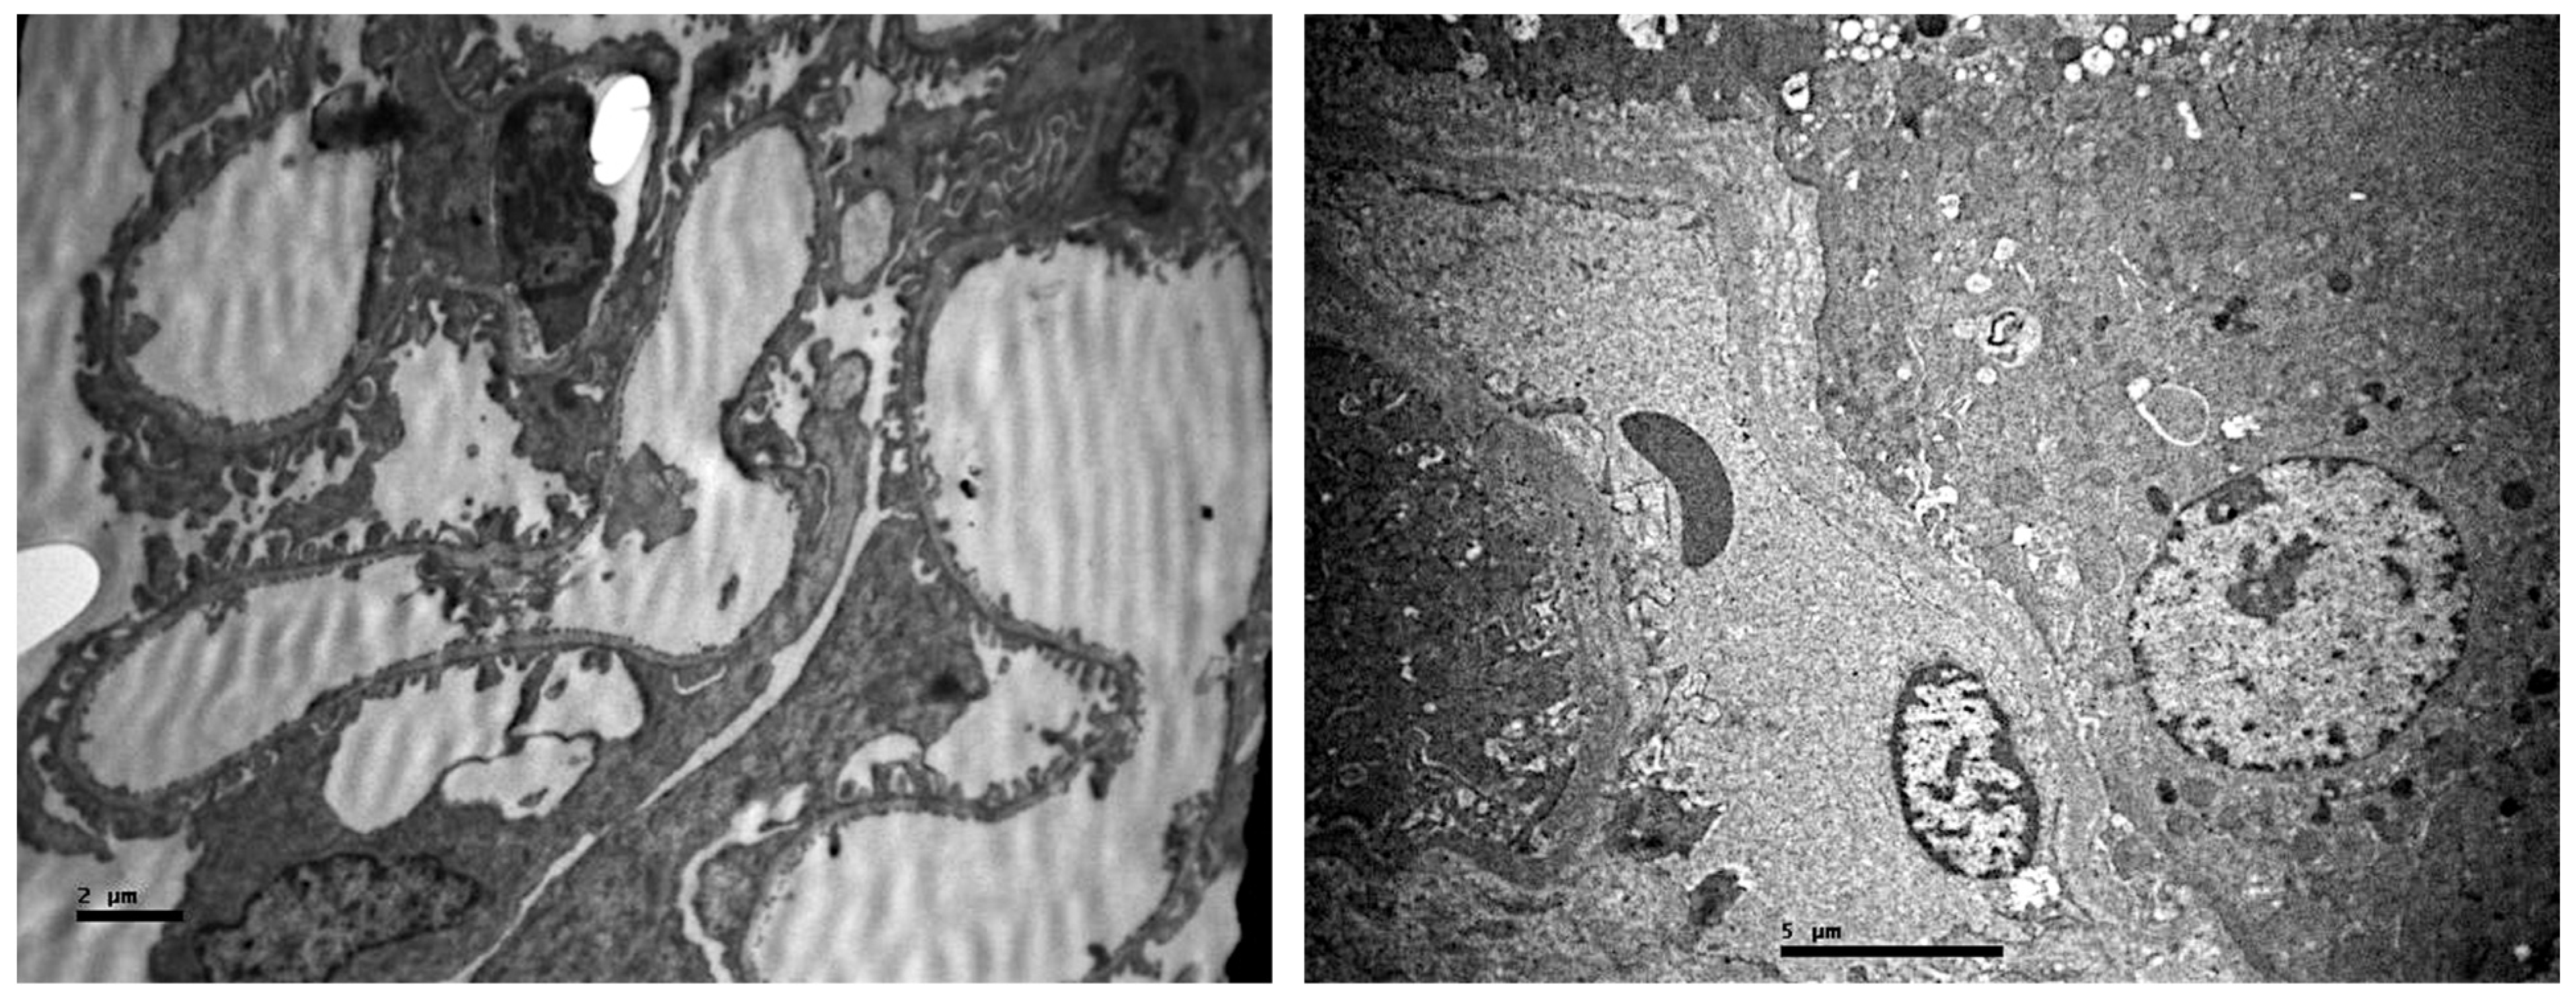

2.1. Light Microscopic Evaluation

2.2. Electron Microscopic Evaluation